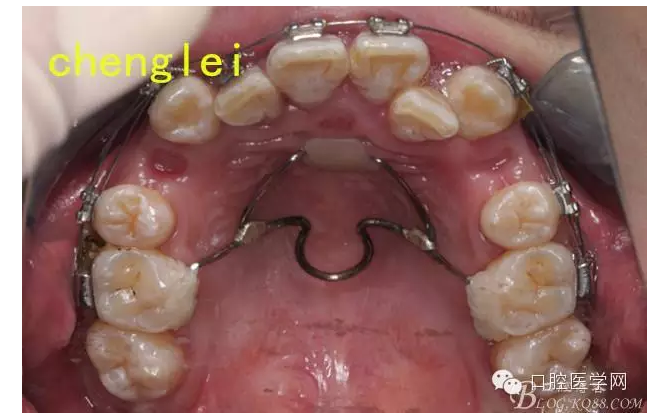

于是為了節(jié)約患者的大量時間,和選帶環(huán)的繁瑣,故采用粘接式的簡易腭桿加nance托。主弓絲為1.0鋼絲,輔弓絲為0.8,之后完成焊接 ,打磨。關于增強支抗抗的手段,武廣增老師習慣應用腭桿和nance 托,效果很好,華西的趙志河老師也強調(diào)過腭桿增強支抗,控制磨牙前移的作用有限,不過nance托可以達到中強支抗。為了達到良好的效果。

由于想法的構思,患者沒有當天戴用,而是,三天以后,約患者過來試戴,圖中可以看出,筆者的nance托并沒有制作,而是空了出來,因為nance托的關鍵,在于與粘膜密貼,而且不能用力壓迫粘膜,又加上 是粘接式的操作,所以為了考慮操作的準確,密合,得當,所以,決定在口內(nèi)粘接完成以后,采用補牙樹脂,用手搓成一個小球,壓在nance弓的鋼絲上,成一個小圓餅狀,就成為了一個nance托,這樣的方法達到了的粘接式nance托與粘膜的密合性,而且口內(nèi)操作,不產(chǎn)熱,采用光固化樹脂完成。還有一個優(yōu)點,完成以后nance托很薄,口感舒適。還有一個操作時間很短,患者進行粘接試戴,到完成只有10分鐘。